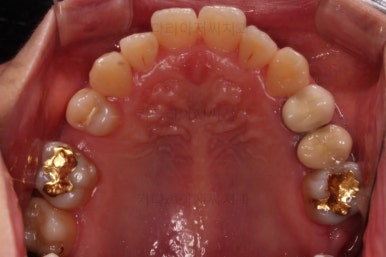

초진 시, 입안의 모습이에요.

결손부위가 눈에 띄고요.

결손부위가 양쪽에 있다보니 윗니 중간에 틈새가 벌어졌네요.

뒤쪽의 빈공간으로 치아들이 도미노처럼 쓰러져서 그렇습니다.

앞니의 약간의 틈새, 약간의 삐뚤어짐, 약간의 중앙선 틀어짐 등 심하진 않으나 약간씩의 문제점들이 있네요.